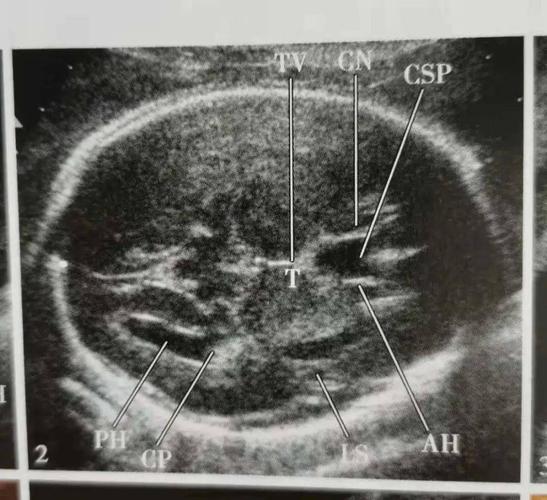

图3-2-20 胎头丘脑平面声像